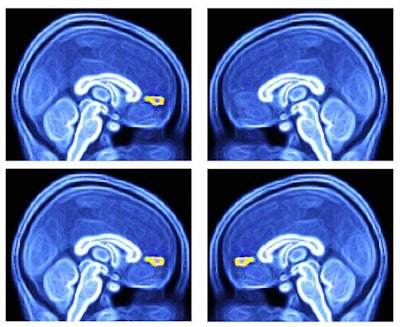

Their approach targets the ventral medial prefrontal cortex, which helps process decision-making. Among the autistic children in this study, the average response in this brain region to familiar faces was significantly diminished, compared with a group of typically developing children. Using fMRI to diagnose autism could take a fraction of the time required for more conventional methods.

For this study, the researchers looked at 44 typically developing children and 24 children diagnosed with autism spectrum disorder (ASD). Functional MRI scans were performed on two 3-tesla MRI scanners (Allegra and Trio, Siemens Healthineers). The researchers targeted the brain's ventral medial prefrontal cortex based on previous studies that showed the region's role in "encoding the value of different types of reward" and as a "critical component of reward processing and decision-making in humans," the authors wrote (Biol Psychol, July 2019, Vol. 145, pp. 174-184).

As the researchers had hypothesized, the functional MR images showed that the average response of the ventral medial prefrontal cortex was significantly lower in the autistic group than among typically developing subjects. That dysfunction related to the autistic children's reduced ability to process their self-chosen favorite faces but not favorite objects.